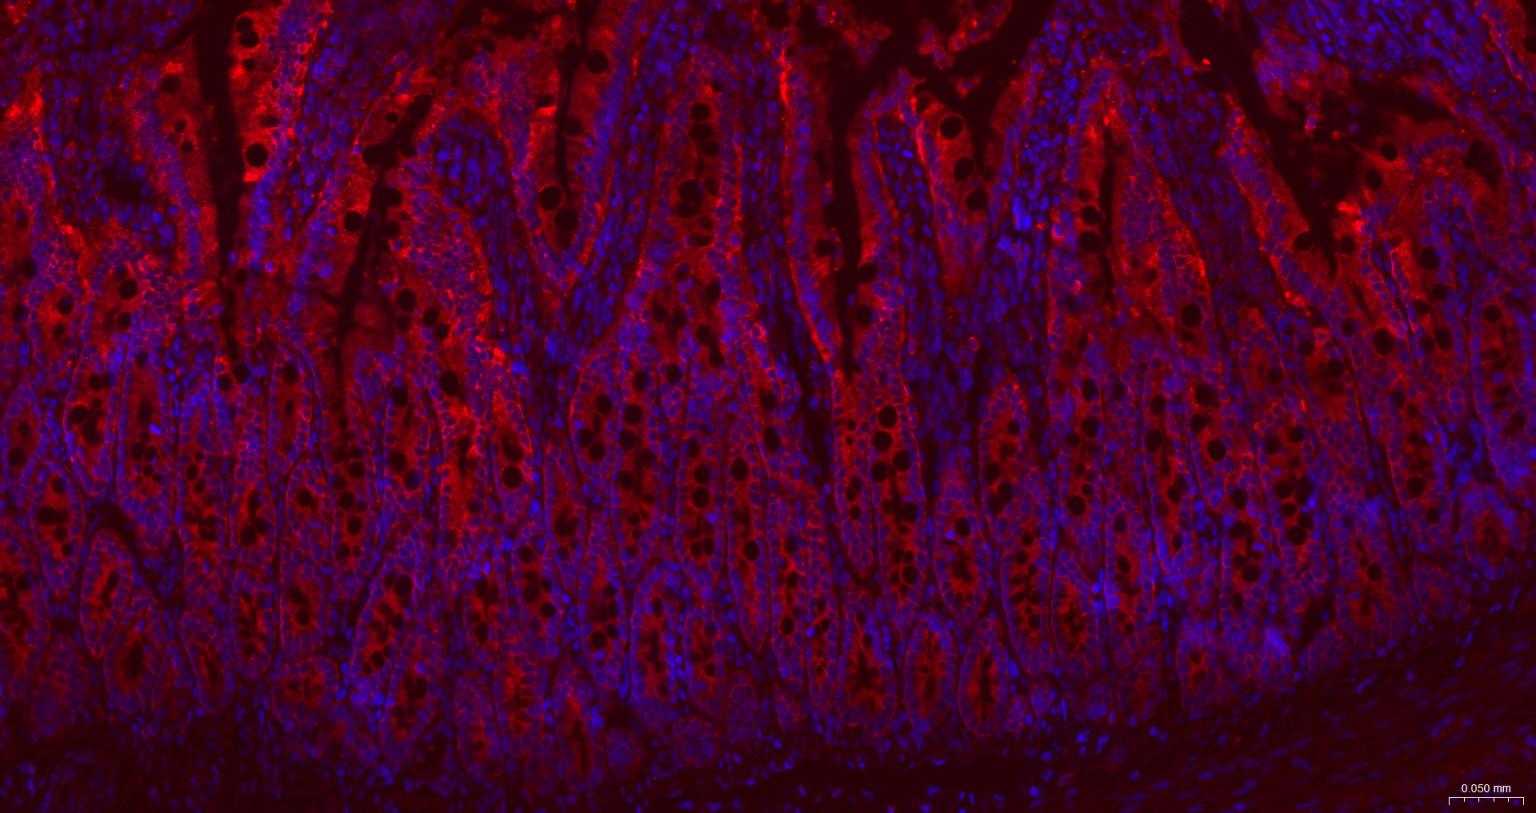

| IHC-F | Human, Mouse, Rat | 1:100-500 | |

| IF | Human, Mouse, Rat | 1:100-500 | |